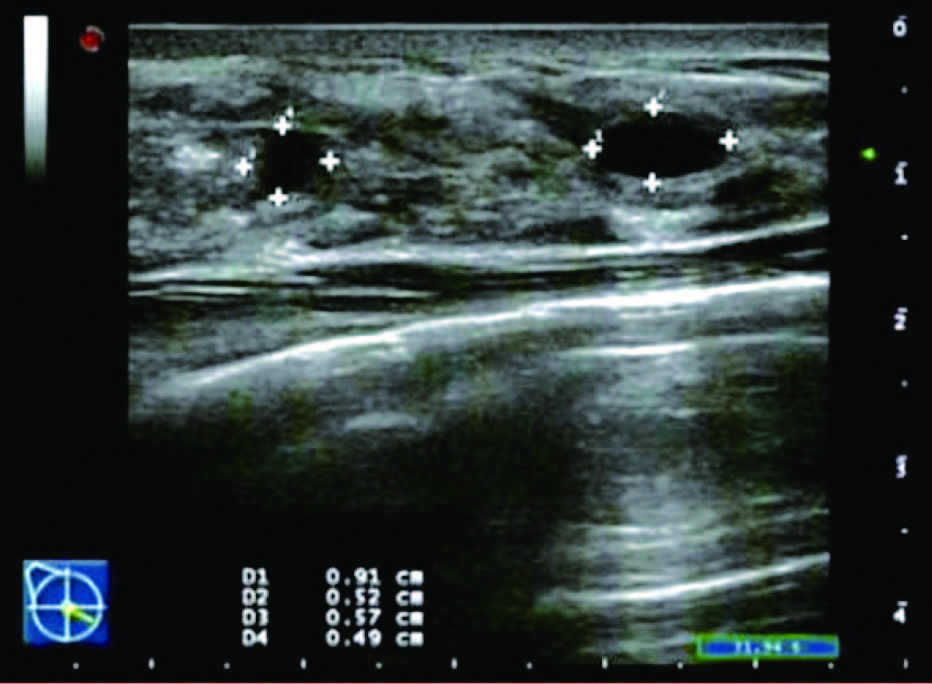

(3)囊性增生型:表现为乳腺组织回声增粗、增强,较杂乱,腺体内可见散在大小不等的圆形或椭圆形囊状无回声或长条形管状无回声区,边界清晰,壁薄光滑,透声好,内部偶见分隔回声带,也可有少许点状回声,内部无明显彩色血流信号。

患者,女,35岁,因双乳疼痛两月,乳头偶有针刺状疼痛,感到胸闷,呼吸不畅来院诊治。超声检查结果显示:右乳内可见多个无回声区,边界清晰,形态规则,其中3点方向较大一个1.7*0.6cm,内可见分隔光带,左乳内可见数个无回声区,边界清晰,形态规则,其中3点方向较大一个大小1.1*0.6cm内可见分隔光带,CDFI探查:未见异常血流信号显示。双侧乳腺切面形态轮廓正常,层次清楚。腺体厚薄不均,边界完整,欠规则,结构紊乱,分布不均,呈片状高回声区。